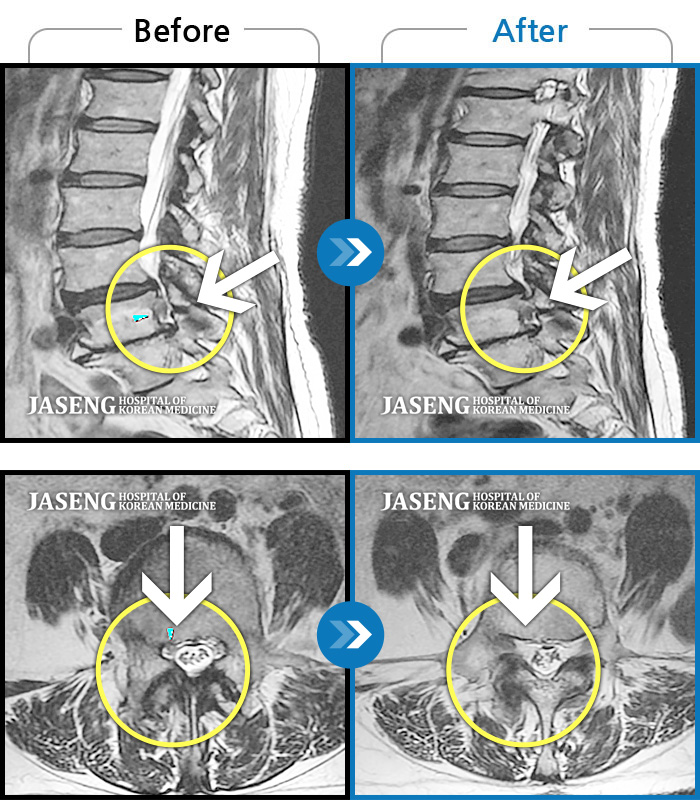

허리디스크

보라매 · 왕오호 원장

허리 통증, 똑바로 서려고 하거나 걸을 때 양쪽 허벅지와 고관절 시큰거림

촬영시기

2017.06.07 ~ 2018.04.17

2018.12.28

조회수 4,172